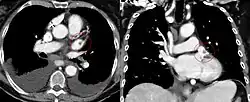

High in the upper part of the left atrium is a muscular ear-shaped pouch – the left atrial appendage (LAA) (lat: auricula atrii sinistra), which has a tubular trabeculated structure.[9] LAA anatomy as seen in a CT scan is characterized as being in one of four groups: chicken wing (48%), cactus (30%), windsock (19%), and cauliflower(3%).[10][11] Cauliflower is the morphology most often associated with embolism.[11] The LAA appears to "function as a decompression chamber during left ventricular systole and during other periods when left atrial pressure is high".[12] It also modulates intravascular volume by secreting natriuretic peptides, namely atrial natriuretic peptide (ANP), and brain natriuretic peptide (BNP) into the coronary sinus, where they enter into the blood circulation.[13]